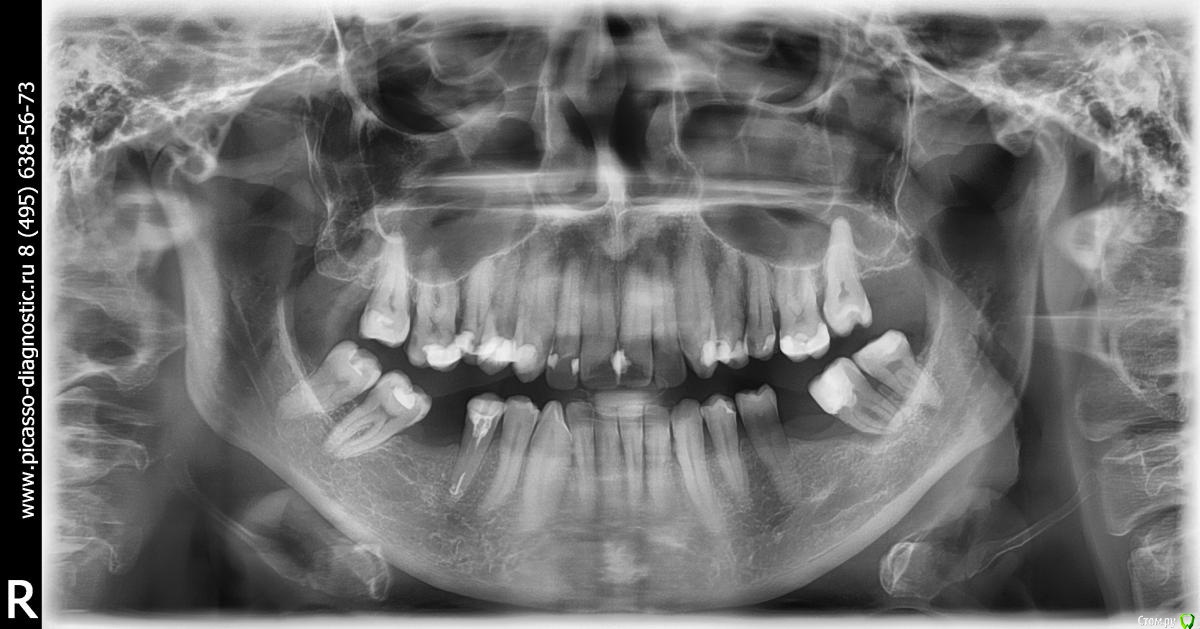

AIR70 Опубликовано 28 июня, 2017 Поделиться Опубликовано 28 июня, 2017 Уважаемые доктора!В настоящий момент прохожу лечение у терапевта, меняю старые пломбы.В процессе возник вопрос о целесообразности сохранения верхней правой пятерки.В зубе достаточно большая пломба, под замену, зуб витальный, расположен небно.В целом, в челюсти зубы скучены.Мой доктор посоветовала проконсультироваться у ортодонта, она предполагает, что после удаления, произойдет разгрузка челюсти с правой стороны и самопроизвольное сдвижение соседних зубов в сторону дефекта.Прошу совета, сохранять зуб или удалить?К полноценному ортодонтическому лечению не готова по ряду объективных причин.Заранее благодарю за ответы. Зуб1.bmp Ссылка на комментарий

AIR70 Опубликовано 28 июня, 2017 Автор Поделиться Опубликовано 28 июня, 2017 Добавляю фото Ссылка на комментарий